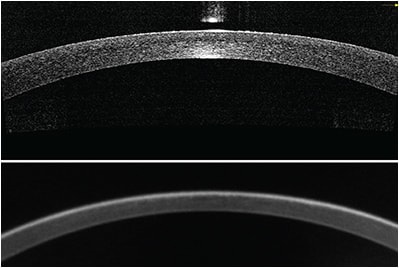

Direct measurement of posterior corneal power is a logical improvement to standard keratometry. The high axial resolution of OCT (Figure, page 41) allows clear delineation of both anterior and posterior corneal boundaries and direct measurement of posterior corneal power, which make it suitable for measuring corneal power.

Figure: Central cornea imaged by a Fourier-domain OCT system (top). The image length is 6 mm and depth is about 2 mm. The eye had previous LASIK but the clinical history was not available. The corneal power was measured to be 38.18 D by automated keratometry. Bottom: The same eye imaged with a rotating Scheimpflug camera topographer. The image length and depth are also 6 mm and 2 mm, respectively. The top image (OCT) appears to have better depth and lateral resolution.